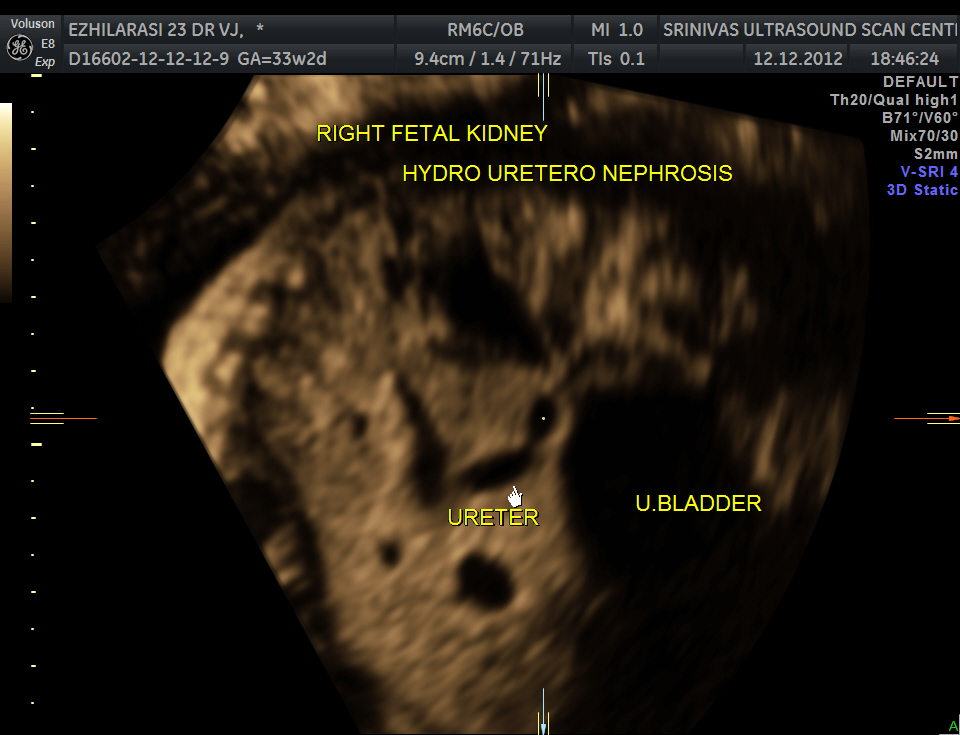

The fetus also showed bilateral pelvi calyectasis and rt ureteromegaly.